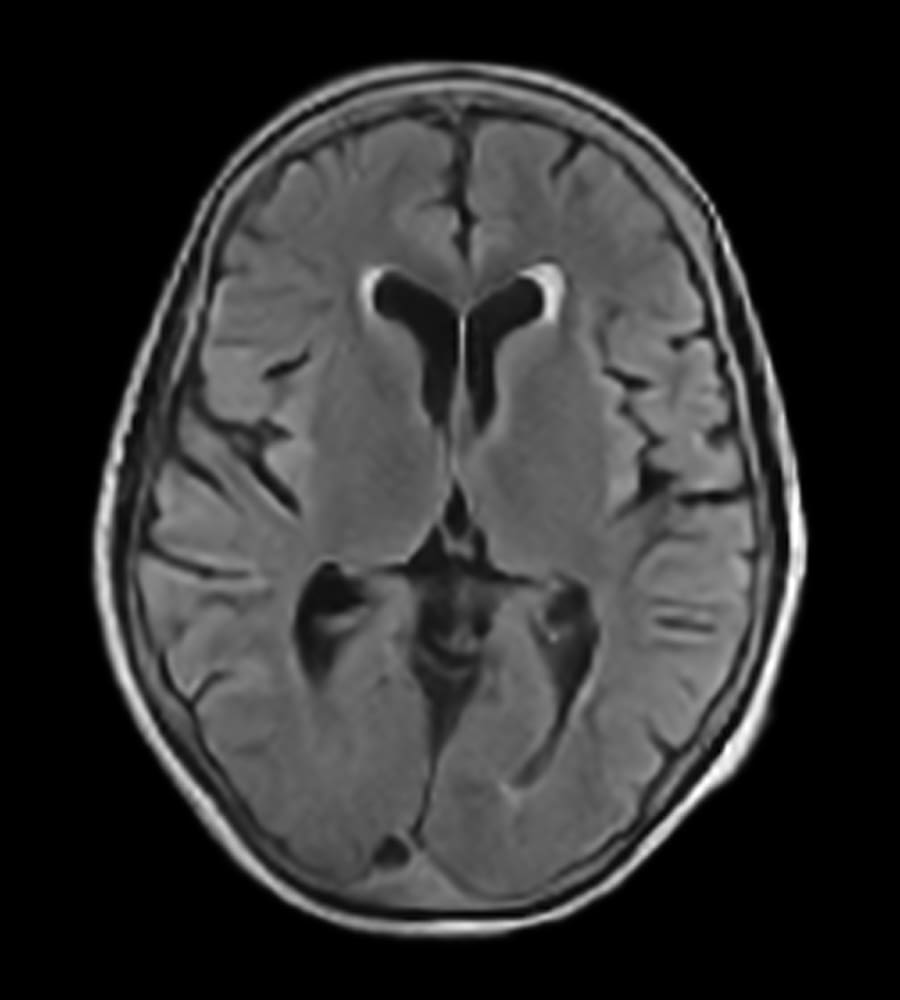

Clinical Images

Clinical case types: Headache, Migraine, Multiple Sclerosis, Micro Vascular Disease and Tumor Routine Follow-up.